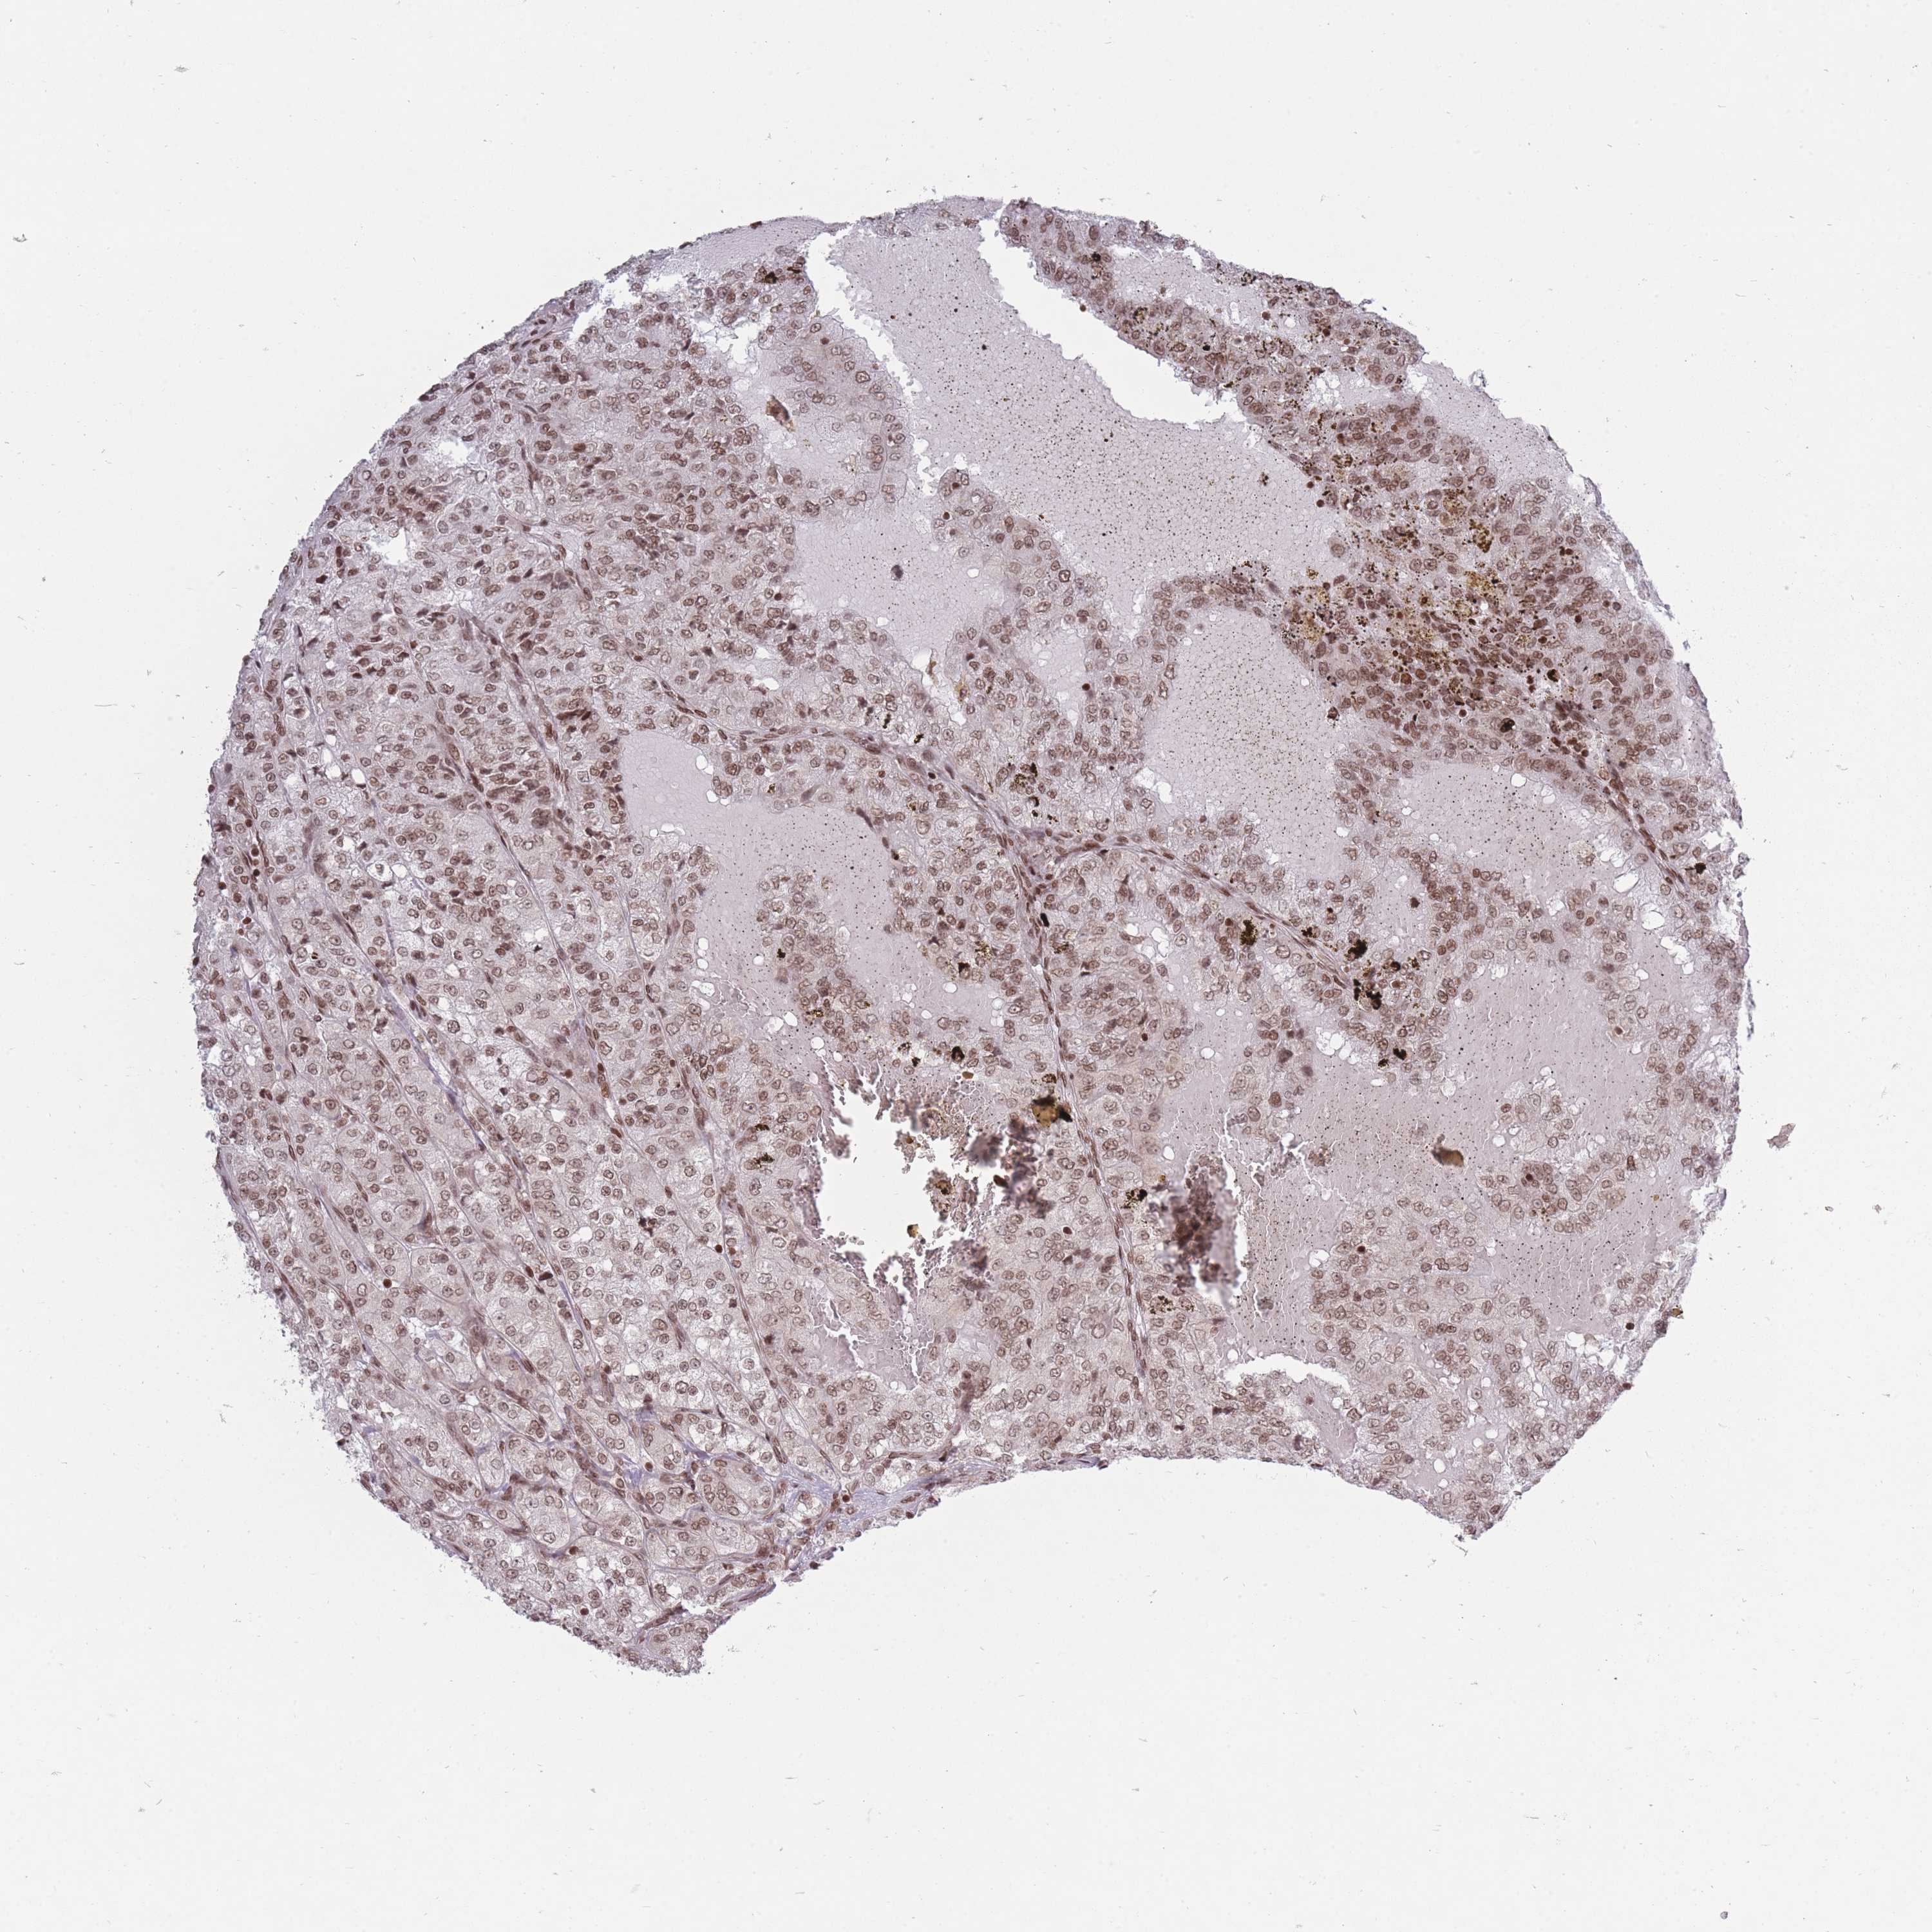

KIDNEY RENAL CLEAR CELL CARCINOMA (VALIDATION) - Interactive survival scatter ploti

The Survival Scatter plot shows the clinical status (i.e. dead or alive) for all individuals in the patient cohort, based on the same data that underlies the corresponding Kaplan-Meier plots. Patients that are alive at last time for follow-up are shown in blue and patients who have died during the study are shown in red.

The x-axis shows the expression levels (FPKM) of the investigated gene in the tumor tissue at the time of diagnosis. The y-axis shows the follow-up time after diagnosis (years). Both axes are complimented with kernel density curves demonstrating the data density over the axes. The top density plot shows the expression levels (FPKM) distribution among dead (red) and alive patients (blue). The right density plot shows the data density of the survived years of dead patients with high and low expression levels respectively, stratified using the cutoff indicated by the vertical dashed line through the Survival Scatter plot. This cutoff is automatically defined based on the FPKM cutoff that minimizes the p-score. The cutoff can be changed by dragging the vertical line or by entering a cutoff value in the square labeled "Current cut-off".

Under the Survival Scatter plot the p-score landscape (black curve; left axis) is shown together with dead median separation (red curve; right axis). Dead median separation is the difference in median mRNA expression between patients who have died with high and low expression, respectively. It is calculated as follows: median FPKM expression of dead patients with high expression - median FPKM expression of dead patients with low expression. This is intended to aid the user in visually exploring custom cutoffs and the associated p-scores and dead median separation.

& Survival analysisi

Kaplan-Meier plots summarize results from analysis of correlation between mRNA expression level and patient survival. Patients were divided based on level of expression into one of the two groups "low" (under cut off) or "high" (over cut off). X-axis shows time for survival (years) and y-axis shows the probability of survival, where 1.0 corresponds to 100 percent.

TMC6 is not prognostic in Kidney Renal Clear Cell Carcinoma (validation)

Best expression cut offi

Based on the FPKM value of each gene, patients were classified into two groups and association between prognosis (survival) and gene expression (FPKM) was examined. The best expression cut-off refers the FPKM value that yields maximal difference with regard to survival between the two groups at the lowest log-rank P-value. Best expression cut-off was selected based on survival analysis .

When clicking on this number, the vertical dashed line indicating cut-off, the interactive survival plot, and the Kaplan-Meier curve will be adjusted to show results based on the best expression cut-off.

: 24.67

P scorei

Log-rank P value for Kaplan-Meier plot showing results from analysis of correlation between mRNA expression level and patient survival.

N/A

Average pTPM 20.9

Number of samples 100